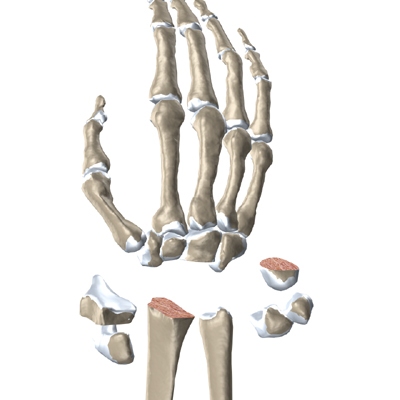

The anatomy of the wrist joint is extremely complex, probably the most complex of all the joints in the body. The wrist joint is actually made up of many joints and many bones. These joints and bones let us use our hands in many ways. The wrist must be extremely mobile to give our hands a full range of motion. At the same time, the wrist must provide the strength for heavy gripping.

The wrist is made up of eight separate small bones, called the . The carpal bones connect the two bones of the forearm, the radius and the ulna, to the bones of the hand. The metacarpal bones are the long bones that lie mostly underneath the palm. The metacarpals are in turn attached to the phalanges (the bones in the fingers and thumb).

One reason that the wrist is so complex is that every small bone forms a joint with the bone next to it. This means many small joints make up the wrist joint. Ligaments connect all the small bones to each other, and to the radius, ulna, and metacarpal bones.